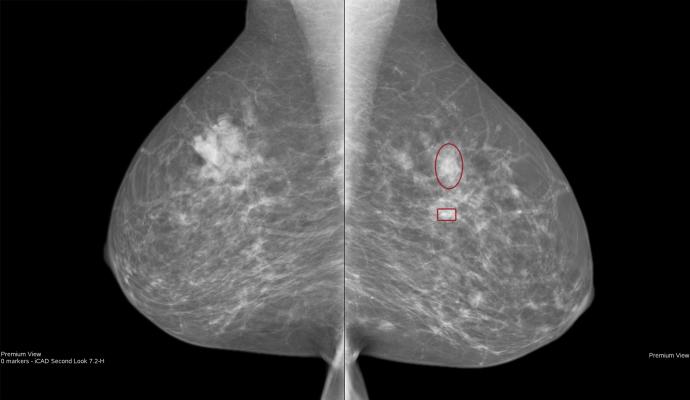

In the near future, Strand intends to look at how breast density is associated with delayed detection. Longer-term, he wants to study artificial intelligence as a way to triage mammographic screening examinations into different pipelines based on the risk of breast cancer and the detectability of a potential tumor.